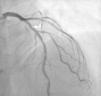

A 12 de março de 2016 foi novamente admitido por episódio de EAMSSST, tendo realizado novo cateterismo cerca de 12h após admissão, que mostrou normal permeabilidade dos vasos previamente tratados, não apresentando sinais de reestenose nos stents previamente implantados, assinalando‐se de novo uma lesão grave suboclusiva com abundante material trombótico a nível da DA, no mesmo segmento em que se identificara uma lesão com uma redução do lúmen de cerca de 30% (Figura 2). A presença de vasoespasmo foi excluída por administração de nitrato intracoronário. No mesmo procedimento, foi realizada angioplastia desta nova lesão com implantação de stent medicalizado e foi usado abciximab como terapêutica antitrombótica complementar. Nas horas seguintes, registou‐se um valor máximo de troponina de 0,30pg/mL (valor normal<0,04 pg/mL), um BNP máximo 59mg/mL e um valor de PCR máximo de 18,6mg/L (valor normal<5,0). A função tiroideia era normal e o estudo de trombofilias foi negativo. O doente permaneceu elétrica e hemodinamicamente estável, mantendo‐se sempre em ritmo sinusal. Teve alta três dias depois, com indicação para aumentar dose de atorvastatina para 80mg e mantendo restante medicação de ambulatório. O ecocardiograma realizado antes da alta apresentava‐se sobreponível, sem novas alterações de motilidade e sem deterioração da função ventricular.